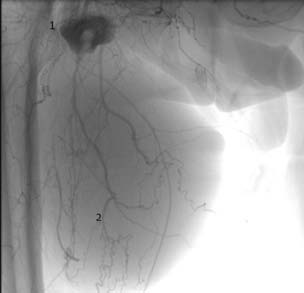

– брюшная аортография: под местной анестезией раствором новокаина (0,25%-ный, 20,0 мл) справа через общую межкостную артерию (локтевая и лучевая артерии окклюзированы). Инфраренальный отдел аорты атеросклеротически изменен, проходим. Справа стеноз общей подвздошной артерии до 60–70 %, наружной подвздошной артерии – до 55 %. Общая (ОБА) и глубокая (ГБА) бедренные артерии проходимы. Из терминальной части общей бедренной артерии контрастируется дополнительное образование размерами 20×16 см, с затеканием контрастного вещества в полость образования. Поверхностная бедренная артерия (ПБА) не контрастировалась на всем протяжении. Через коллатерали фрагментами выполняется подколенная (ПКЛА) и малоберцовая артерии. Слева окклюзия подвздошных артерий на всем протяжении (рис. 1).

Рис. 1. Артериографическая картина гигантской аневризмы проксимального анастомоза АВБПШ: 1 – просвет аневризмы; 2 – тромбированная полость аневризмы